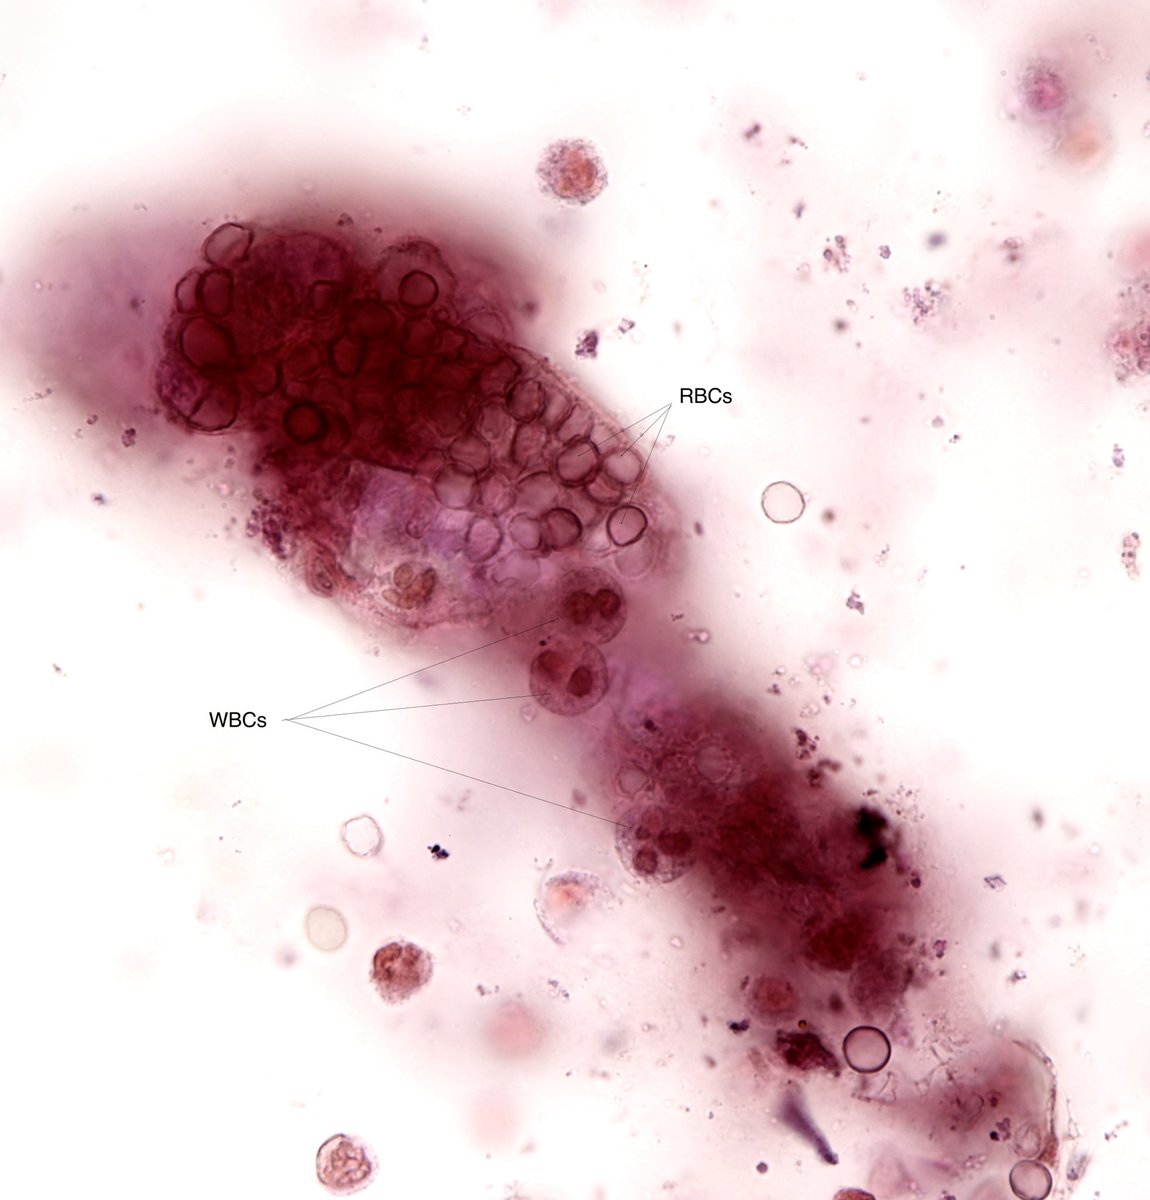

RBC cast ( and a few WBCs) - brightfield, with SM stain - from patient with septic arthritis and bacteremia - #UrineMicroscopy #UrinarySediment